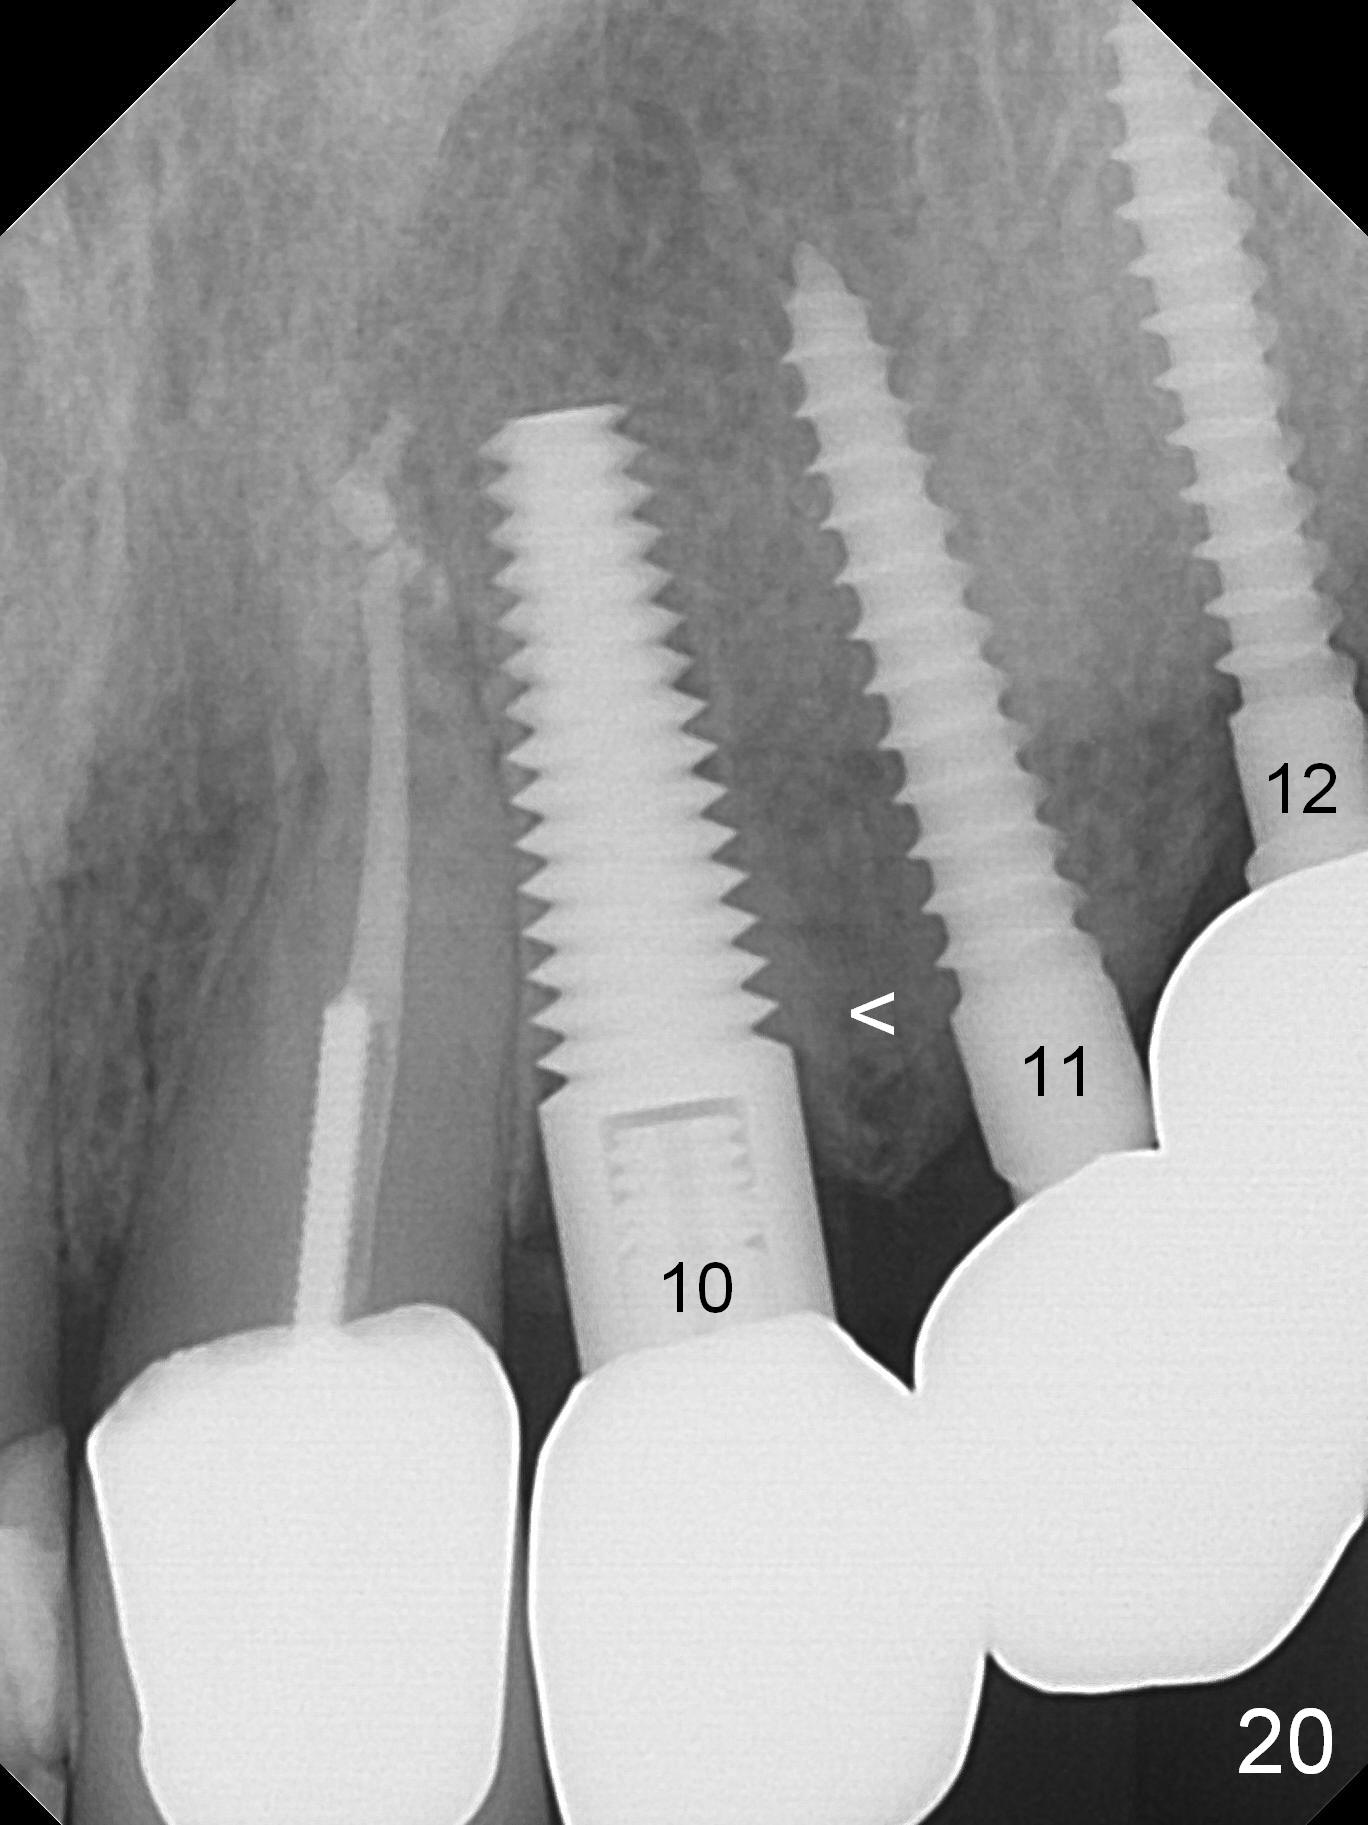

When the patient returns for implant placement (2nd visit after initial exam), he reveals that he is a dental phobic.  He requests placement of 4 implants in the upper left quadrant, instead of 2.  Narrow ridge is unexpected in the canine and premolar area (Fig.1).  Limited bone height at #13 (Fig.3 arrowheads: sinus floor) is found when initial drills are in place (Fig.2,3).  A 2-piece implant (4.5x17 mm tissue-level) is placed at #10 after extraction, while 1-piece implants are placed at 11 (3x17 mm (tissue-level, 15 °) and 12 and 13 (bone-level, 2.5x14, 12 mm, respectively; Fig.4,5).  In fact the 1 piece implant at #13 is not completely placed (Fig.5).  It is removed, the apical 3 threads are cut off (Fig.6 <, since a shorter implant was unavailable in the office) and the remaining implant is re-inserted.  The insertion torques of the 4 implants are ~ 60, ~ 35, < 35 and 15 Ncm, respectively.  After adjustment (Fig.7), immediate provisionals are fabricated at #10 and 11 (Fig.8, later splinted with composite), while perio dressing is applied around the implants at #12 and 13 and the provisionals at #10 and 11.  There is no nasal hemorrhage postop.  Although the perio dressing is loose 1 week postop (Fig.9), it is not removed.  When the upper lip fissure (Fig.9 <) heals, provisionals at #12 and 13 are planned to be splinted to the other two ones.  Two weeks postop, the upper lip fissure heals, the perio dressing dislodges and the implants at #12 and 13 are stable (Fig.10).  After abutment height adjustment, a splinted provisional is fabricated over these 2.5 mm 1-piece implants (Fig.11).

Six months post cementation, the tooth #9 becomes symptomatic.  Is it possible that the implant at #10 is too close to the root of #9?  It is asymptomatic after pulpotomy, but the tooth fractures equi/supragingivally.  Two PAs taken while RCT show osteointegration at #10-12 (Fig.18,19).  While the bone density increases at #10 regular implant, there is minimal bone loss around the 1-piece implants 13 months post cementation (18 months postop, Fig.20,21).  The gingiva remains healthy 19 months post cementation (Fig.22).  76岁病人突然打电话说一个植牙牙冠松动,其实9号牙(自然牙)折裂,6,10-13号牙植牙好像没有骨质吸收(图二十三至二十五),10-13牙位牙龈健康(图二十六,行使功能五年)。9号牙牙冠重新粘固后,显示前牙深覆合,深覆盖(图二十七,二十八)。如果再次脱落需要植牙,选择一段式有助于植入和修复,因为植体和基台直径小。两段式植牙相对基台直径至少4,或者4.5毫米,前牙修复显得笨重。由于9,10牙根和植体接近,9号牙植体需要偏小而长,3x14或者15毫米(图二十九)。